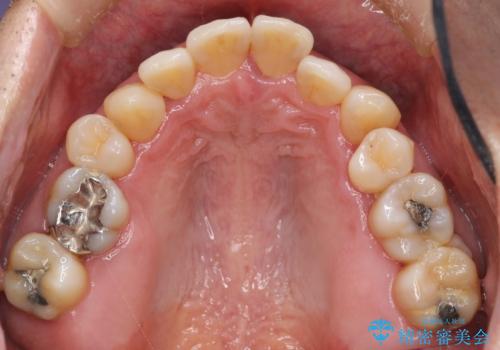

- 「仕事のリタイヤに目処がつき、今後は自分の健康にお金をかけたい。しっかりと食事ができる口腔内環境にしてほしい。」と全体的な治療を希望され来院されました。

全体的に重度の歯周病が認められ、抜歯が必要な部位はインプラント治療を、残すことのできる歯には再生治療を含めた歯周病治療を行い全体的な治療を進めてきます。